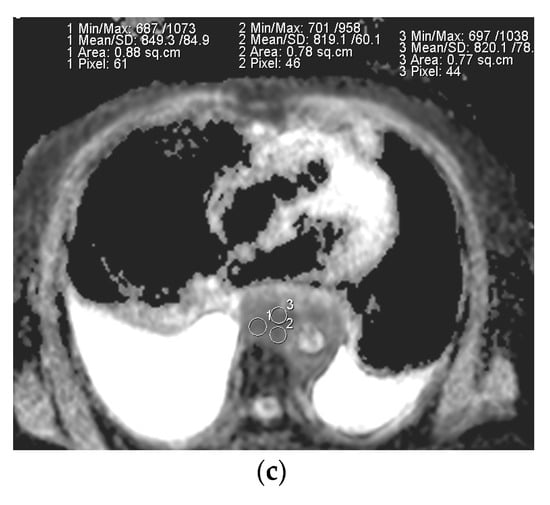

The representative T2-weighted images, DWI, and ADC maps of the malignant and benign lymph nodes are shown in Figure 2 and Figure 3 respectively.

Figure 2.

(a) T2-weighted axial MRI of a 75-year-old male shows a T2 homogeneous signal in enlarged lymph nodes encasing descending thoracic aorta; (b) Diffusion-weighted axial MRI shows diffusion restriction in most of the lymph node; (c) System generated ADC map of corresponding lymph node shows ADC mean value of 0.829 × 10−3 mm2/s. The final pathological diagnosis was lymphoma.